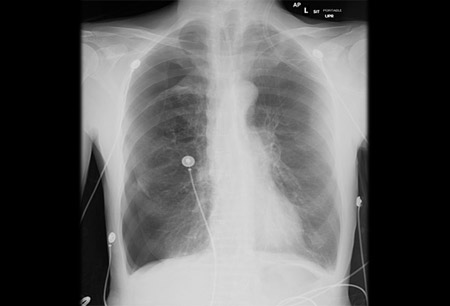

Diagnostic investigations